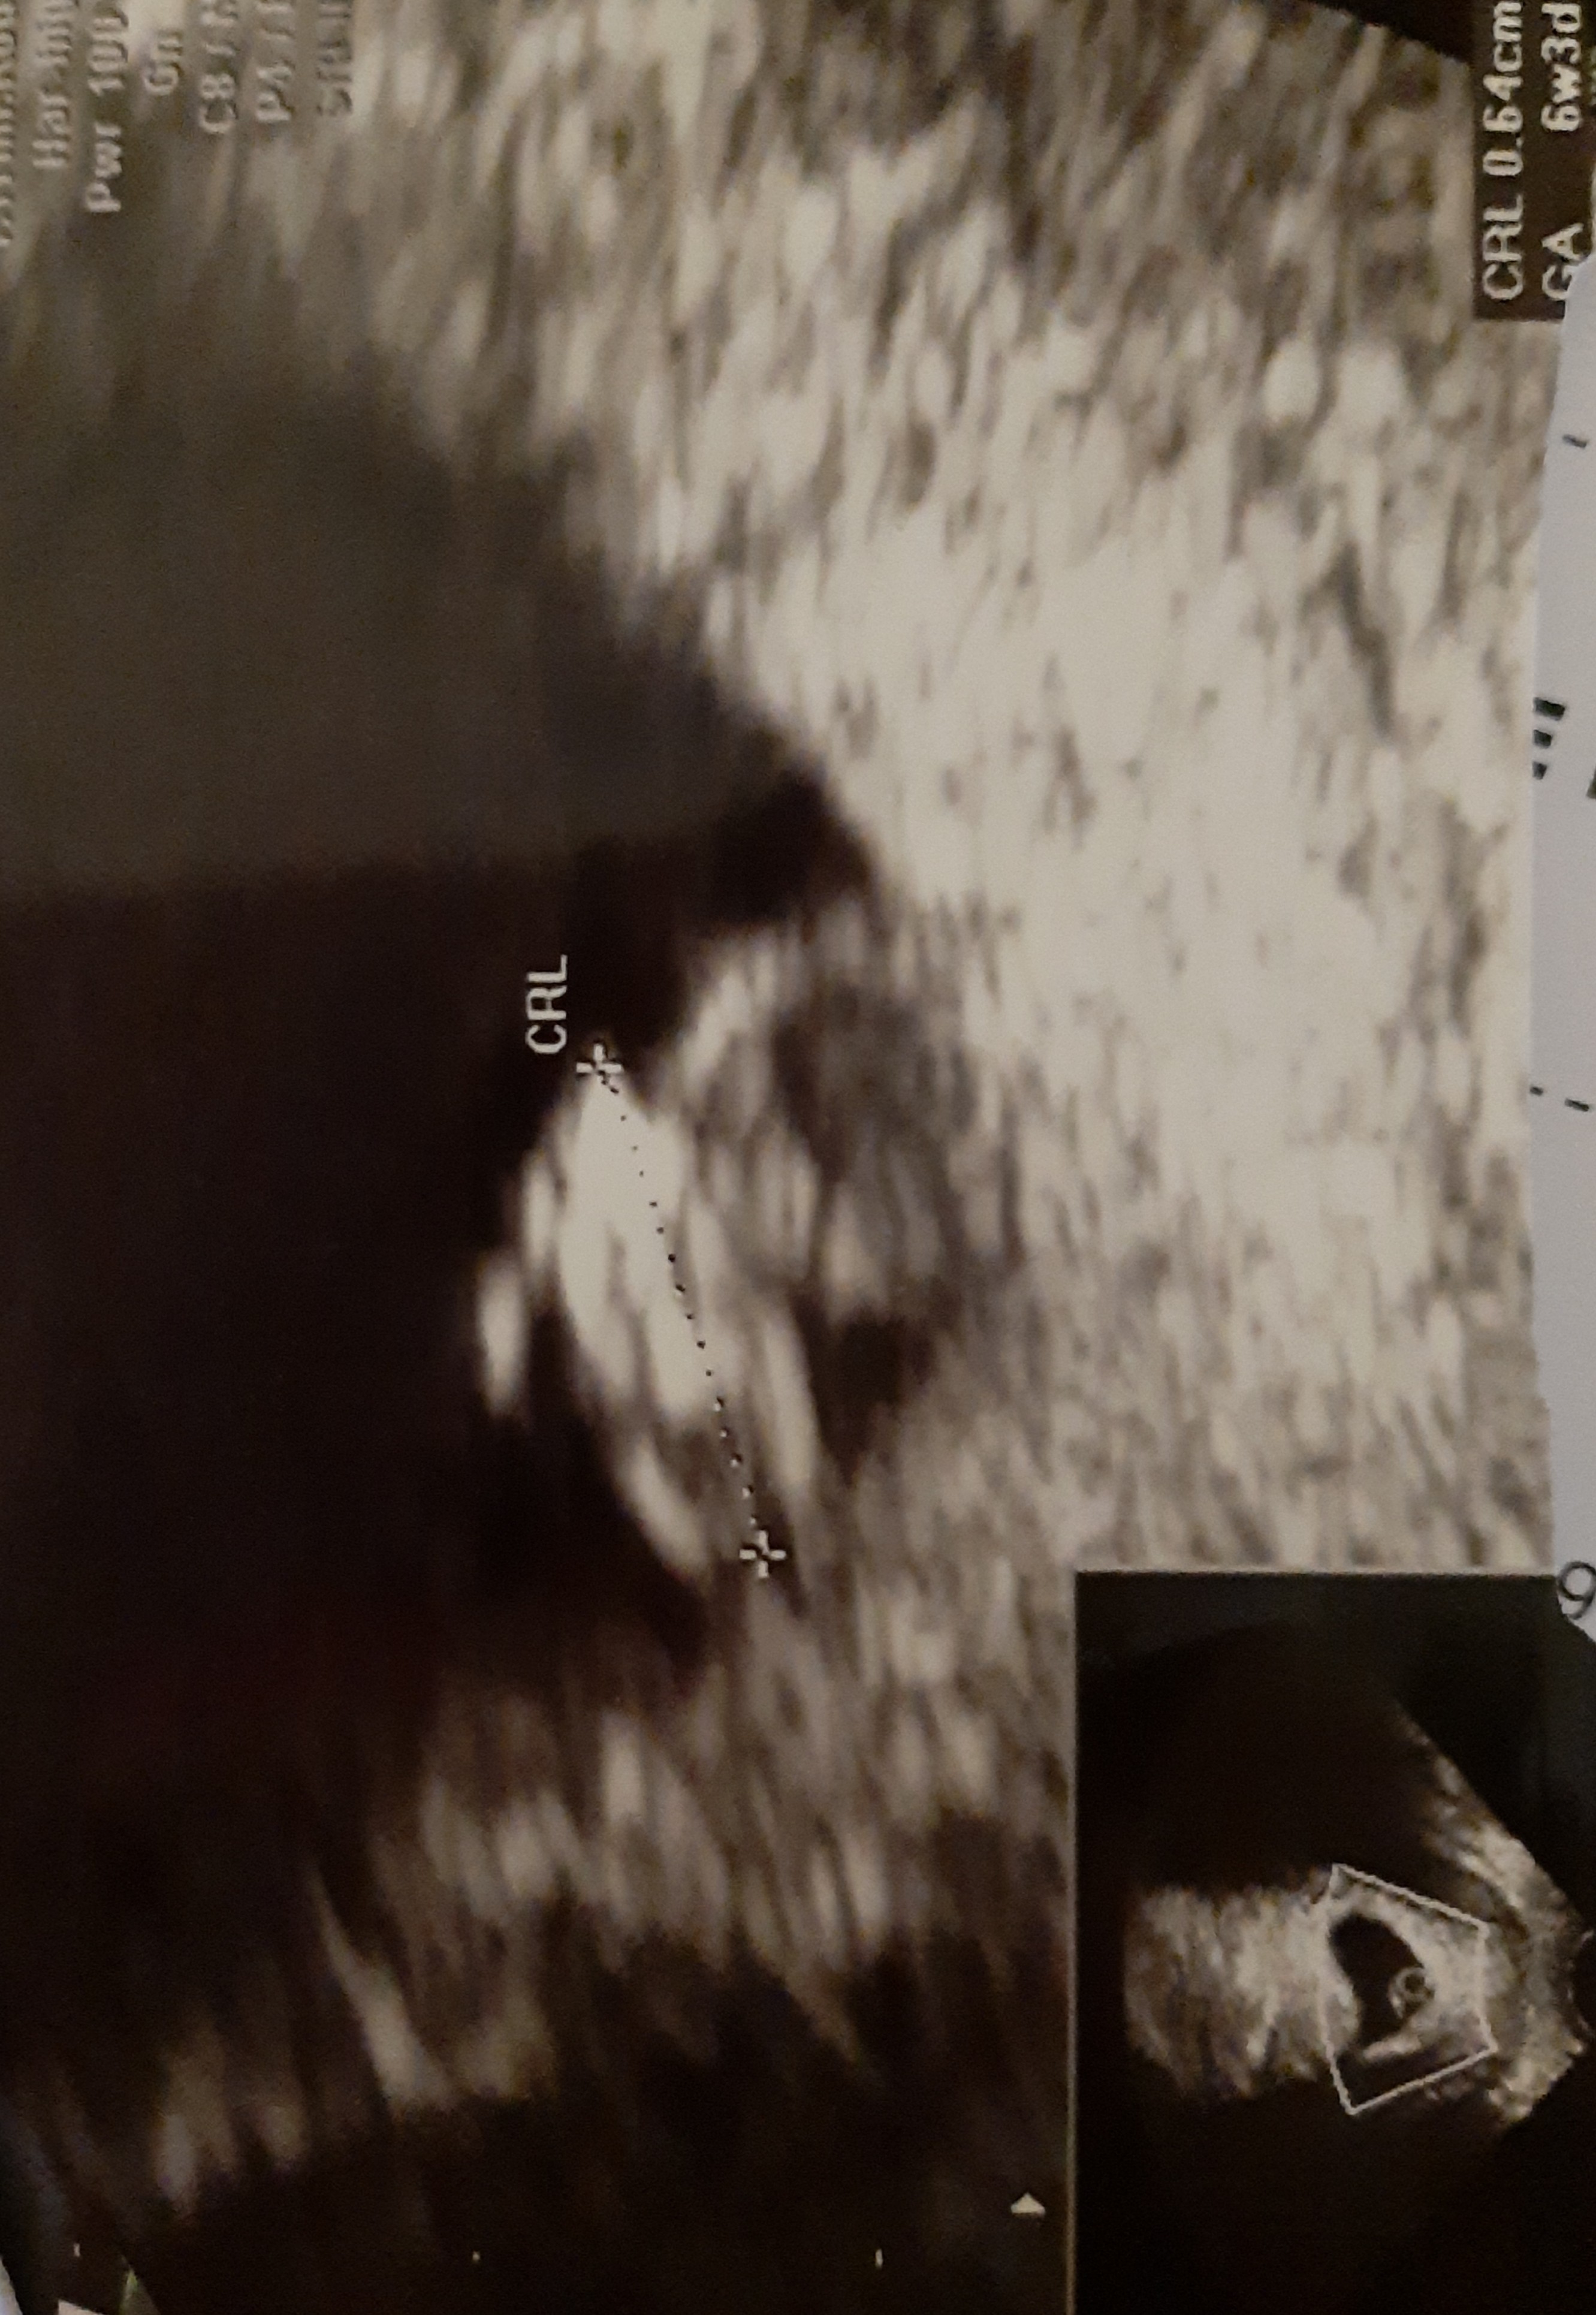

Nasze wizyty i zdjęcia USG :)

W końcu też mogę się pochwalić zdjęciem usg.

9 tydzień.

Jest serduszko ❤.

16 mm